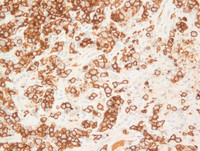

CD30

Strong CD30 expression is noted in the lymphoma cells that are also seen to be intrasinusoidal.